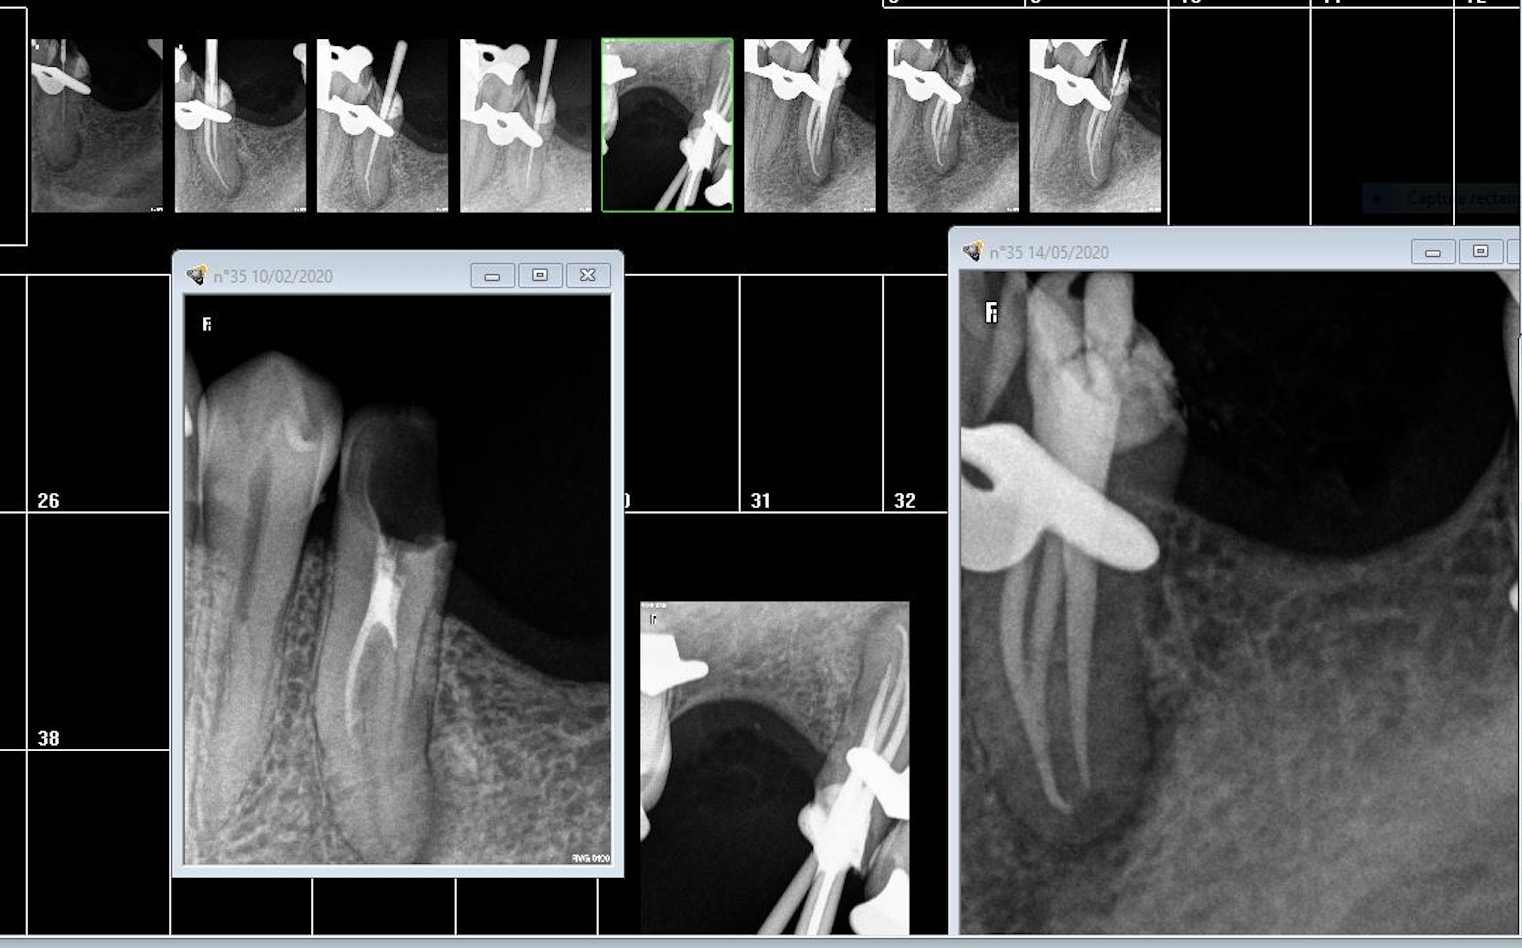

Tyyh72nq8zxg8vkvtmicno17ligs - Eugenol

Que de radios ! Tu devrais investir dans un localisateur d’apex ☝️

Quand tu fais ta radio de contrôle t’as encore la digue, tu devrais l’enlever puisque je raconte n’importe quoi, tu pourrais prendre de meilleurs radios ☝️

Non ça marche très bien comme ça et le localisateur ne te dit pas dans quel canal tu es

Une radio broche en place te donne une idée des courbures et de la distance à la quelle tu es de l'apex surtout dans les cas complexes. . Des infos que le localisateur ne te donne pas.